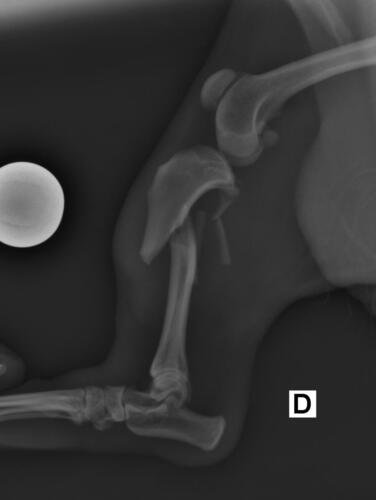

Olá, me chamo Jacqueline sou a mãe do chokito de 4 patas 🐶. No dia 07/02/2025 chokito foi atropelado em frente a minha casa, onde resultou no quadril dele quebrado e a patinha direita traseira quebrada tbm (a tíbia). Quem atropelou ele não parou pra prestar socorro a ele, e mto menos quis saber oque havia acontecido. Chokito foi atropelado na frente dos meus filhos, duas crianças um autista de 5 anos e uma criança de 3 anos, onde o acidente poderia ter acontecido com um deles, mas graças a Deus, Deus livrou eles, mas infelizmente o chokito não. Desde o dia 07 o chokito sofre de fortes dores constantes, onde ele não consegue se movimentar, para se alimentar ele precisa de ajuda, pra beber água, está com dificuldade em evacuar por conta das fortes dores que ele vem sentindo. Preciso de ajuda pra dar uma qualidade de vida pro chokito voltar a andar e parar de sentir dores constantes. A cirurgia ficou em torno de R$5,500 reais, um valor ao qual eu não consigo pagar, tudo tem sido mto caro, tenho gastado com remédios, Raio x, veterinário, já a cirurgia está mto a cima do que eu poderia pagar pra ajudar ele. Chokito é um cachorro que já foi abandonado e maltratado, pegamos amor e cuidamos dele, meus filhos sofrem por não poder brincar com o cachorro deles e ver o cachorro sempre gritando de dor é uma tristeza para todos nós. Por isso preciso de ajuda pra custear essa cirurgia que ele tanto precisa. Por favor quem puder me ajudar de alguma forma pra que ele volte a andar e parar de sofrer. Estou com meu coração dilacerado vendo ele sofrer sem poder fazer mais do que eu já estou fazendo que é cuidar dele. Cada dia que passa é mais tempo que ele passa sofrendo e agravando a situação que ele se encontra.